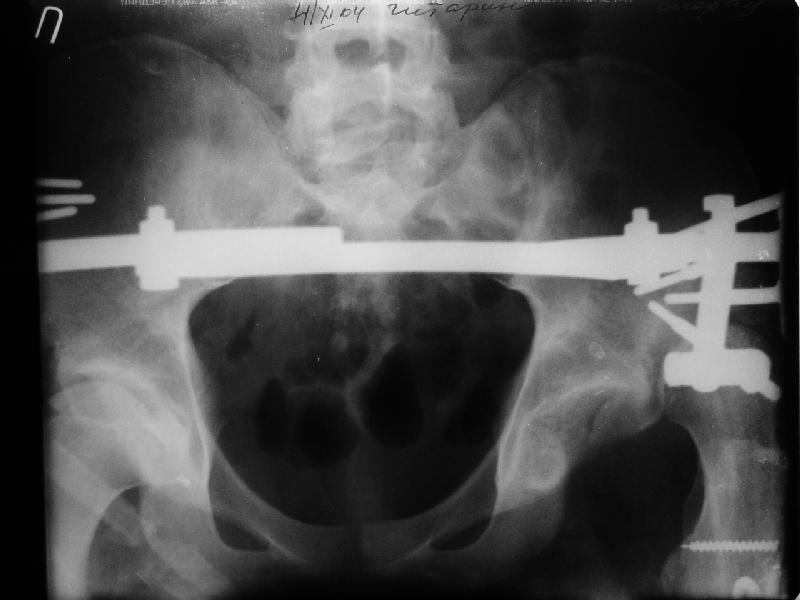

Просьба простить за длительное молчание, не было фотоаппарата, чтобы перенести рентгенограммы. Больного прооперировали в прошлый четверг, как и предполагали, голень проблем не доставила(настолько, что даже не ввели дистальные винты по ряду причин: срок после травмы, целая малоберцовая, последующая длительная ходьба без нагрузки, да и гвоздь сел плотно). Изначально планировали после удаления фиксатора антеградно завести стержень и утопить конец, но вопрос был исчерпан, когда выяснилось, что все имеющиеся стержни слишком длинные, пришлось ретроградно забить большеберцовый гвоздь, после рассверливания; серьезные проблемы возникли с устранением ротации. В вертельной области сломали стержень-джойстик(привет установщику эндопротеза), дальнейшие манипуляции проводили пучком спиц и стержнем с кондуктором. Закончили все аппаратом таз-бедро. Решили что возможные огрехи с ротацией устраним после открытого вправления. Снимки прилагаю. Спасибо за участие в обсуждении. Обязуюсь информировать о дальнейших этапах лечения.